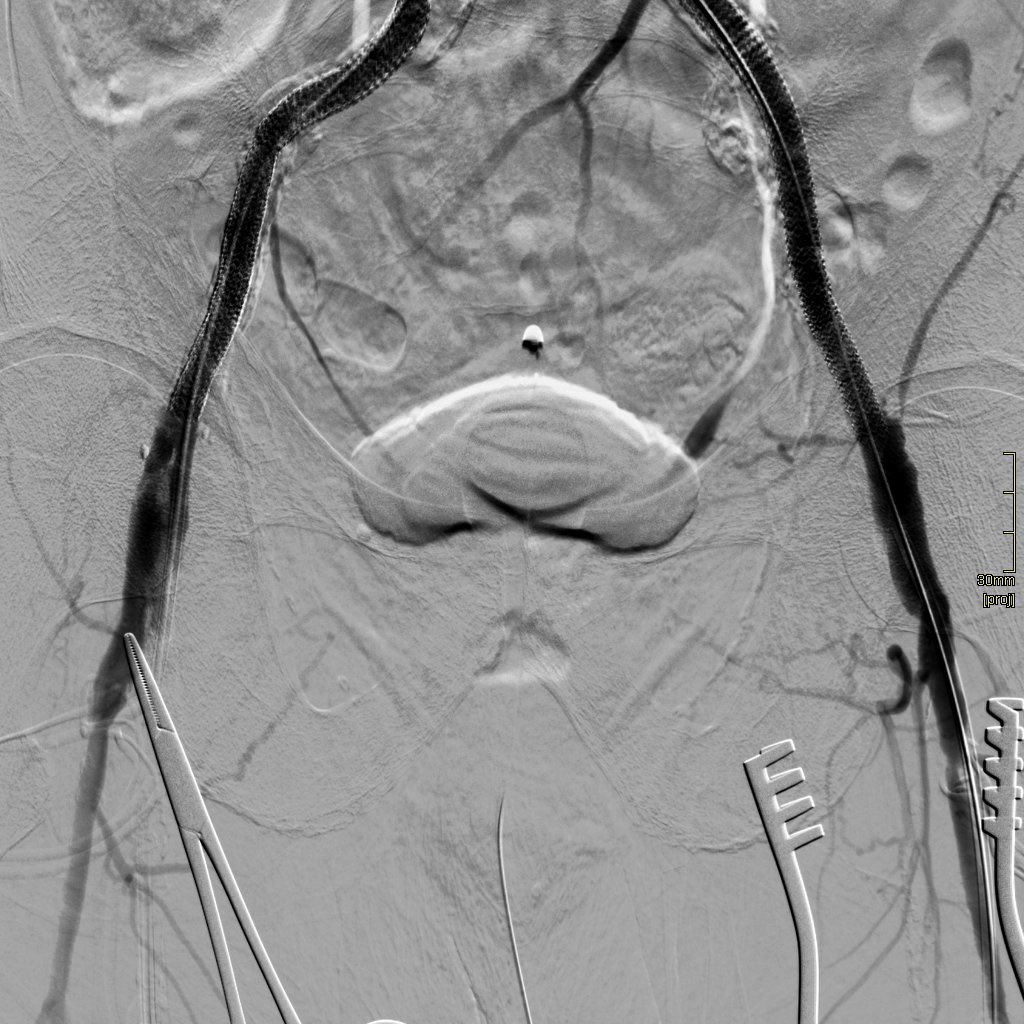

Day 4 at @NHSHarlow, some #IR to entertain you during #selfisolation! A case of severe aortic-iliac disease with ++ bilateral calcification/stenosis of distal Aorta and prox. CIAs.

Subintimal recannalisation and stenting (CERAB technique) by Zaid A H Aldin. Complicated by embolisation to R Fem A, Rx’d by embolectomy. Stents extended bilaterally to inguinal’s with good result.

Subintimal recannalisation and stenting (CERAB technique) by <a href="/ZaidAHAldin1/">Zaid A H Aldin</a>. Complicated by embolisation to R Fem A, Rx’d by embolectomy. Stents extended bilaterally to inguinal’s with good result.

We’ve found stenting to just above inguinal ligaments is essential in severe diffuse iliac disease - to reduce risk of embolisation/dissection. #Irad #withoutascalpel PAIRS Mark Gregory